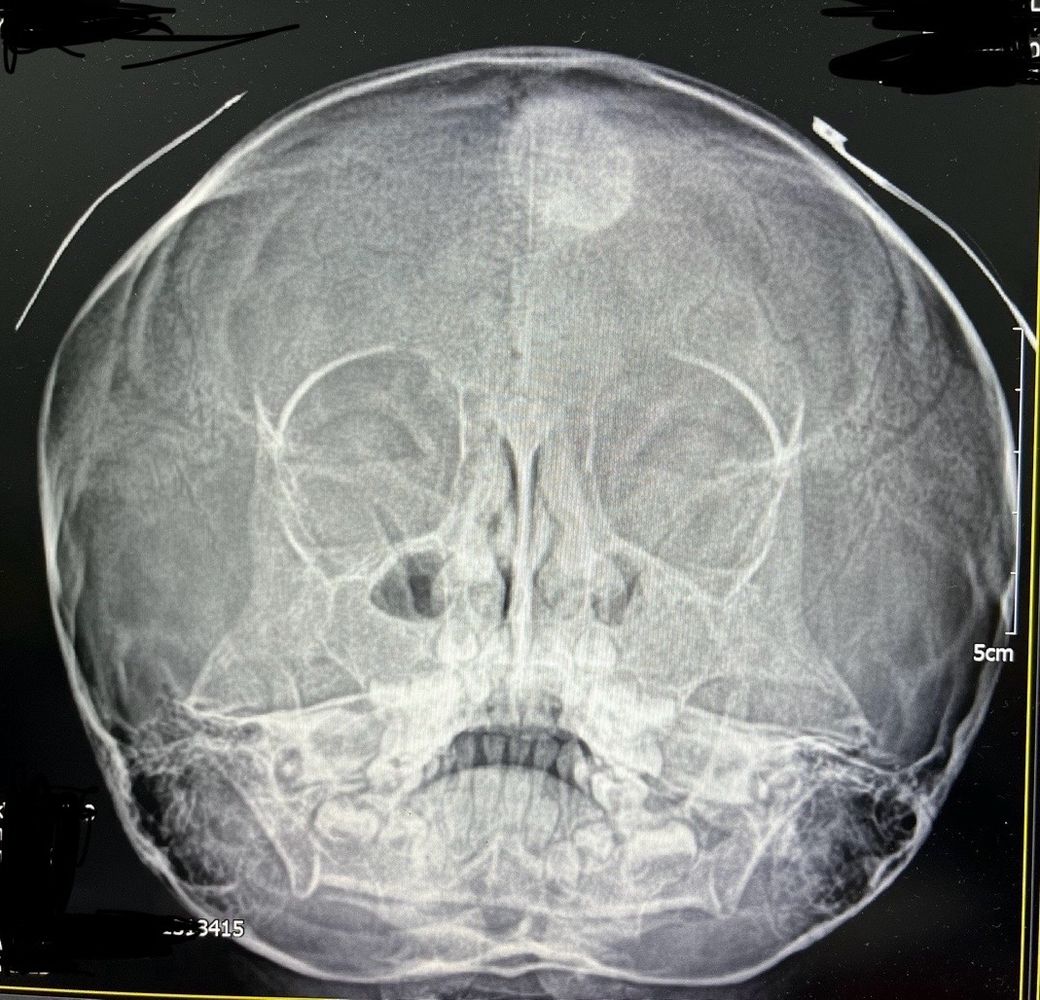

5세 여아입니다 얼마전 부비동 엑스레이사진 입니다

머리에 흰색 원이 보이는데요

소아과 원장님도 처음 보는거라시네요

무엇일까요?

진료 보려면 무슨과가 좋을까요?

처음보는 소견인 것은 마찬가지입니다만, 엑스레이 사진으로는 정확하게 무슨 문제인지 파악하기는 어렵습니다. 보다 정밀한 검사를 통해서 파악이 필요해 보입니다. CT 검사를 통해서 일단은 더 자세하게 파악을 하는 것이 필요해 보이는 상황입니다. 진료과는 신경외과로 가시는 것이 가장 적절할 것으로 사료됩니다.